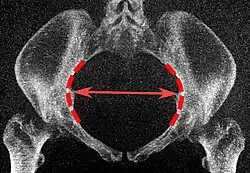

| Abertura superior da pelve | Diâmetro transverso da abertura superior | ![]() |

As linhas iliopectíneas, na maior distância transversa. | 13 a 14,5 cm.[4] |